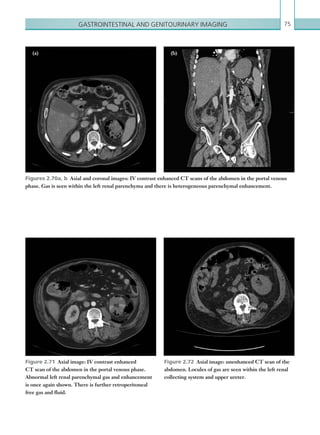

Figure 1.13  PA chest radiograph. Area of peripheral

consolidation at the left mid zone representing an area

of peripheral lung infarction.

Figure 1.14  Axial image: IV contrast enhanced

CT scan of the pulmonary trunk in the arterial phase.

There are features of chronic pulmonary emboli with

recannalised embolic material seen along the walls of the

right main pulmonary artery (arrow).

Figure 1.15  Axial image: IV contrast enhanced

CT pulmonary angiogram. The diameter of the main

pulmonary trunk is greater than the diameter of the

ascending aorta at that same level, suggesting pulmonary

hypertension. The cause is chronic pulmonary emboli

completely occluding the right main pulmonary artery.

Figure 1.16  Axial image: IV contrast enhanced

CT scan of the thorax in the arterial phase. Mosaic

attenuation of the right upper lobe is shown as a result

of abnormal pulmonary perfusion in chronic embolic

disease.